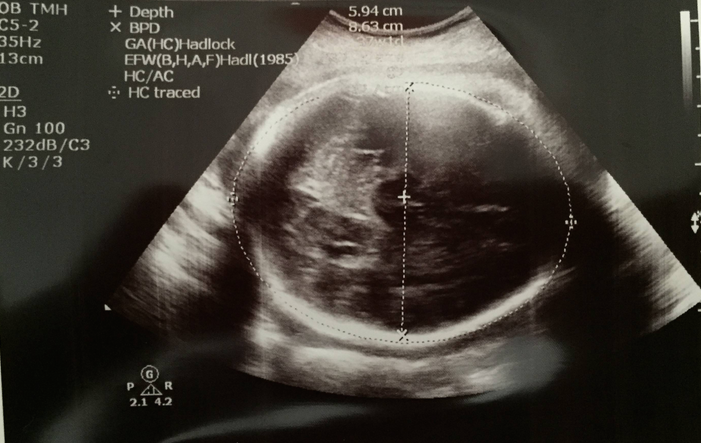

頭仔﹗S醫生話而家難啲量度啦,因為頭仔開始少少engage入盆骨裡面,今日估計大概1/5吧,所以頭仔會被盆骨壓得扁扁地,而且可能側側地,個plane未必咁完美,加上啲骨頭阻住超聲波penetrate,裡面嘅detail都冇之前睇得咁清楚了~